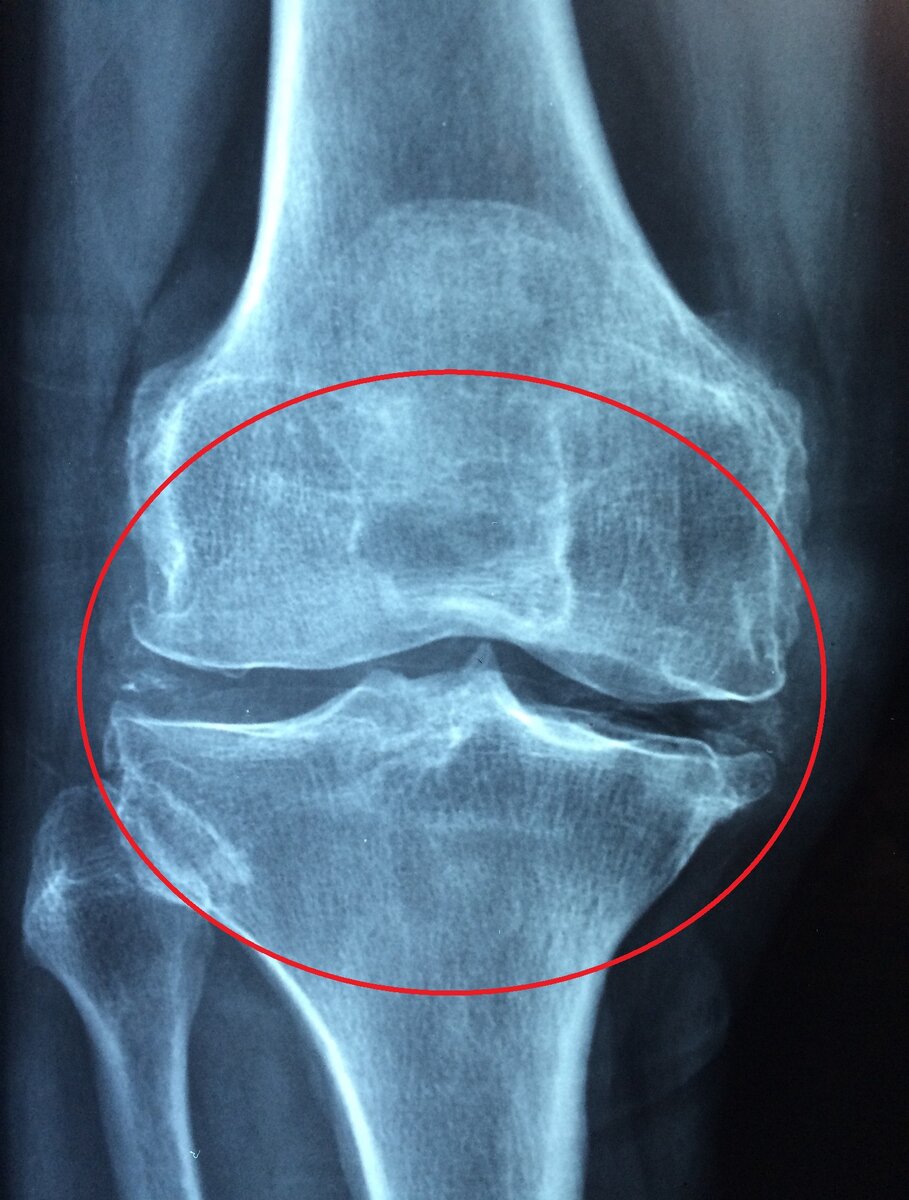

1 Заболевания опорно-двигательной системы.